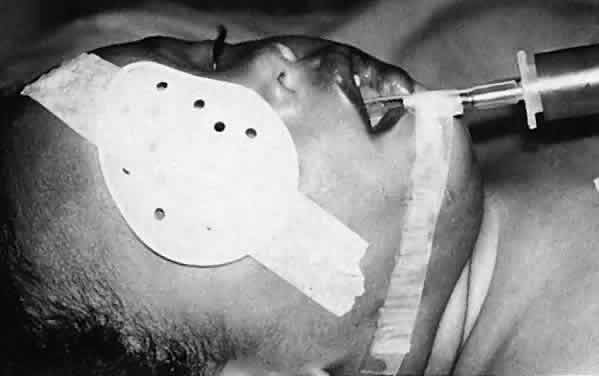

Ultimately, it is the measured or estimated level of visual acuity or acuity potential that determines the need for cataract surgery. If either the measured or the estimated decrease in visual acuity produced by the cataract is sufficient to prevent adequate visual development or if signs of significantly decreased visual acuity, such as strabismus or poor central fixation, are present, cataract surgery is indicated. Use of the Teller visual acuity cards at periodic intervals can help to measure visual acuity.10 In some children, visual acuity that is below normal or decreasing can be documented accurately to support the decision to perform cataract surgery (Figs. 4 and 5). Care must be taken in interpreting Teller visual acuity data because the normal levels in young infants and children are low and span a wide range. The Teller acuity card measurement of grating visual acuity may severely underestimate the level of visual loss in patients with cataracts and amblyopia.11